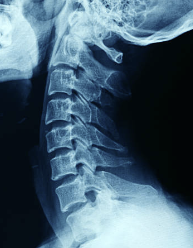

우리 목 뒤쪽엔 여러 신경들이 머리로 지나가게 되어 있고, 이 부분에 압박이 느껴지면

뒷골이 땡기는 듯한 느낌을 받는다고 합니다.

그리고 목디스크로 인해서도 신경이 눌려 통증과 함께

뒷목이 땡기는 증상을 받을 수도 있습니다.

목뼈 사이엔 디스크가 있는데 이것이 돌출이 되면서 일어나는 증상입니다.

디스큰 아니지만 일자목 역시 뒷목 땡김에 큰 영향을 끼칩니다.

사람의 목은 C자 커브가 된 상태가 건강한 상태인데,

1자의 상태가 되면 디스크에 무리가 가고

목과 어깨에 무리가 가기 때문에 뒷골 당김 현상이 생길 수 있습니다.